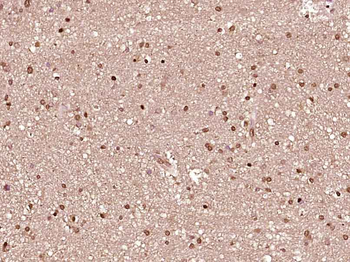

RARB Rabbit Polyclonal Antibody [orb11327]

FC, ICC, IF, IHC-Fr, IHC-P, WB

Bovine, Canine, Gallus, Porcine, Rat

Human, Mouse

Rabbit

Polyclonal

Unconjugated

50 μl, 100 μl, 200 μlTIG2 Rabbit Polyclonal Antibody [orb11481]